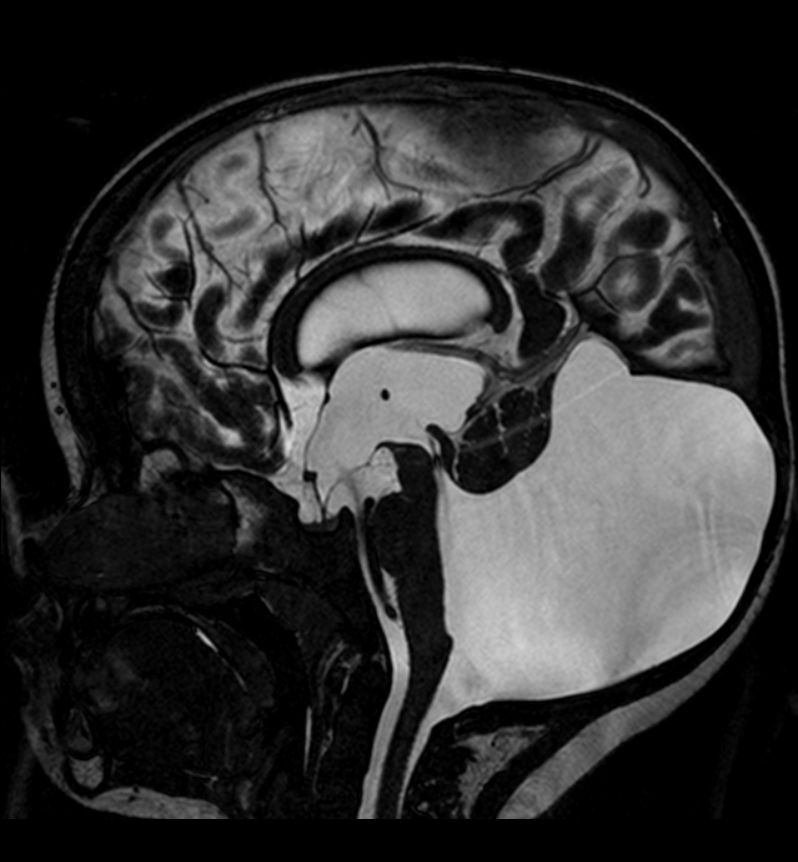

МРТ снимки мальформации Денди-Уокера